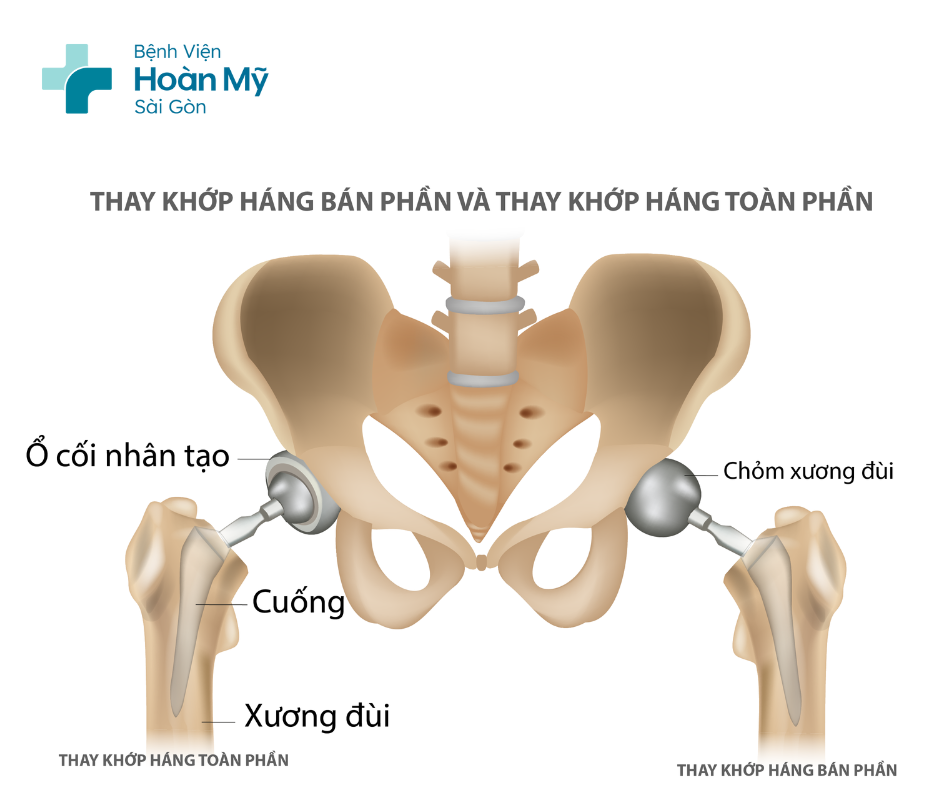

Thay khớp háng toàn phần

Thay toàn bộ phần mặt khớp của xương đùi và ổ cối. Phẫu thuật này được chỉ định khi bệnh nhân bị các tổn thương khớp như thoái hóa, hoại tử vô khuẩn… và kỹ thuật này có thể thực hiện thay 2 bên cùng lúc giúp bệnh nhân lấy lại chức năng vận động sớm hơn.

Thay khớp háng bán phần:

Chỉ thay thế phần chỏm xương đùi mà không thay thế ổ cối; đây là phẫu thuật được chỉ định các trường hợp chấn thương gãy cổ xương đùi ở người già, hoặc những trường hợp thể trạng yếu không thể đảm bảo thực hiện thay khớp háng toàn phần.